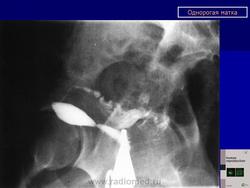

МПС. Женская репродуктивная система. Аномалии и варианты развития. Матка. Однорогая матка. +

Аномалии и варианты развития. Однорогая матка.